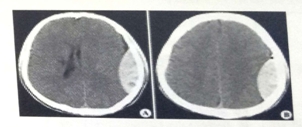

试题2:男,44岁。头部外伤12小时。结合CT片,此诊断为(2分)

A.硬膜下血肿

B.脑出血

C.硬膜外血肿

D.颅骨骨折

E.脑血栓

答案:C